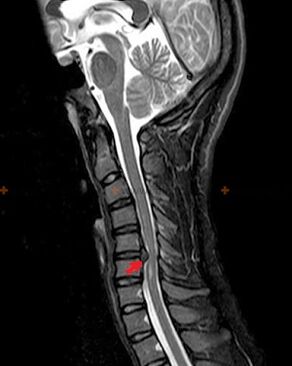

Diagnostics and X-ray signs

Osteochondrosis is an X-ray diagnosis, since a detailed clinical picture is present only at the moment of exacerbation, while when a person is in complete subjective well-being, changes in the spine may occur.Without an X-ray examination, one can only speak of a suspicion of osteochondrosis, since similar symptoms can also be caused by other diseases (myositis, vertebral neoplasia, etc.).

To diagnose osteochondrosis, the following examination methods are used: radiography (preferably with functional tests), MSCT and MRI.The latter study is the most preferable as it allows a very clear visualization of the condition of the intervertebral structures.

The presence of the changes described above, as well as changes in the structure of the intervertebral disc detected by MSCT and MRI, serve as reliable signs of the presence of osteochondrosis.